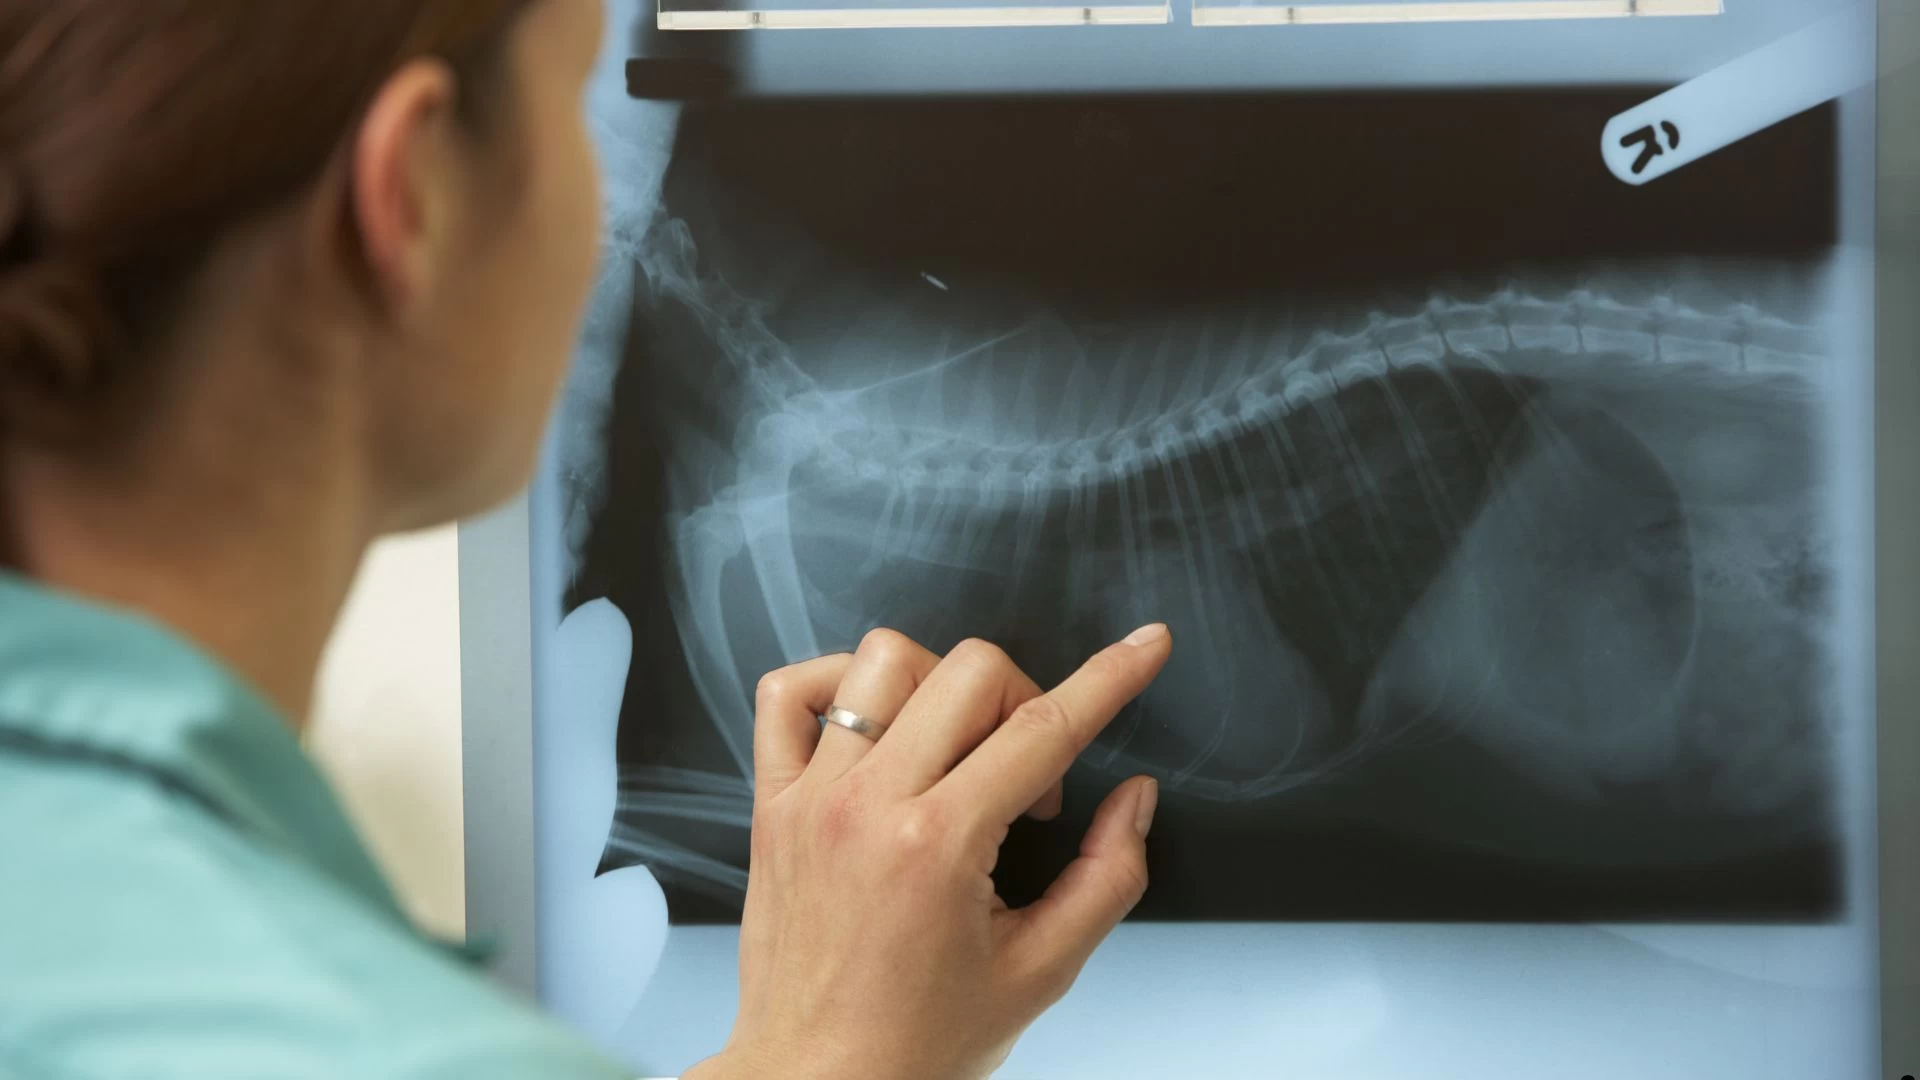

Imagem (radiografia e ultrassonografia)